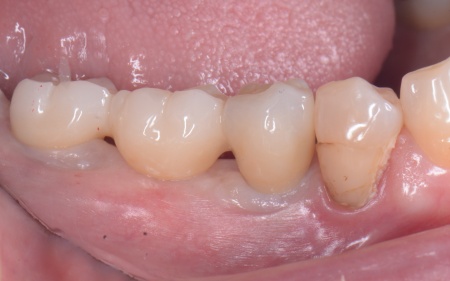

50代女性 歯根が割れた奥歯を抜いてインプラントで噛み合わせを回復させた症例

3ヶ月後、インプラントと骨がしっかりと結合したことが確認できたため、被せ物を作製するための型取りを行います。

被せ物には、人工ダイヤモンドと呼ばれるほど高い強度をもつ、ジルコニアセラミックを使用したブリッジを製作しました。

後日、完成した被せ物を装着し、見た目や噛み合わせに問題がないことを確認して、治療を終了しています。